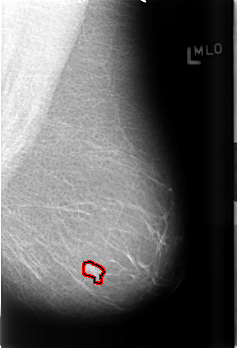

B_3433_1.LEFT_MLO

LEFT_MLO LINES 4512 PIXELS_PER_LINE 3072 BITS_PER_PIXEL 12 RESOLUTION 50 OVERLAY

FILE: B_3433_1.LEFT_MLO.OVERLAY

TOTAL_ABNORMALITIES 1

ABNORMALITY 1

LESION_TYPE MASS SHAPE IRREGULAR MARGINS ILL_DEFINED

ASSESSMENT 4

SUBTLETY 4

PATHOLOGY BENIGN

TOTAL_OUTLINES 1

BOUNDARY